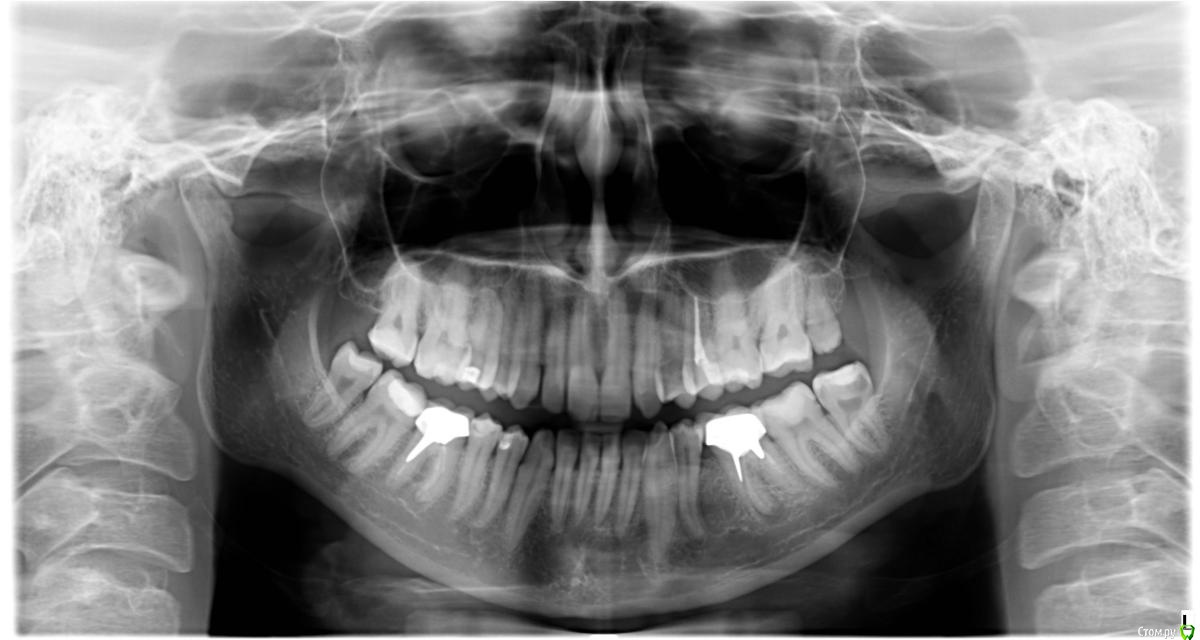

Добрый день! На снимке на корнях двух нижних шестёрок есть гранулемы. Эти зубы были пролечены резорцин-формалиновым способом когда мне было 14 (сейчас 29). Зубы были с огромной пломбой, впоследствии одна из стенок отвалилась. Позже при перелечивании этих зубов пылились распломбировать каналы, заливали какую-то жидкость на час, но безуспешно. Оставили так, 5 лет назад так как от зубов мало что осталось и выглядели они неэстетично, решила поставить коронки. Протезист предупредил, что каналы до конца не пролечены, пролечить их очень сложно и есть риск потери зуба, в итоге оставили как есть, по максимуму санировали, поставили вкладки и коронки. Зубы не болят и практически не беспокоят, хотя в последнее время та шестерка, которая не со светлой гранулемой пульсирует, немного тянет десна под ним и соседними зубами.

Добрый день. Та 6 которая слева выглядит хуже, если будет беспокоить я бы ее удаляла, потому что от стенок корня сейчас осталось мало, штифты  большие, если их доставать то скорее всего от зуба совсем ничего не останется и очень большой риск трещины в зубе сейчас и в будущем.

По правой 6  принимать решение по ситуации. Если не беспокоит - наблюдать и ничего не делать, если будет болеть то по ситуации, можно пробовать достать вкладку и перелечивать(но вероятность успеха 50/50) можно удалять и имплант. Зависит от вашего настроя и желания.

Еще по снимку на 8 слева похоже кариес достаточно обьемный, очень близко к нерву